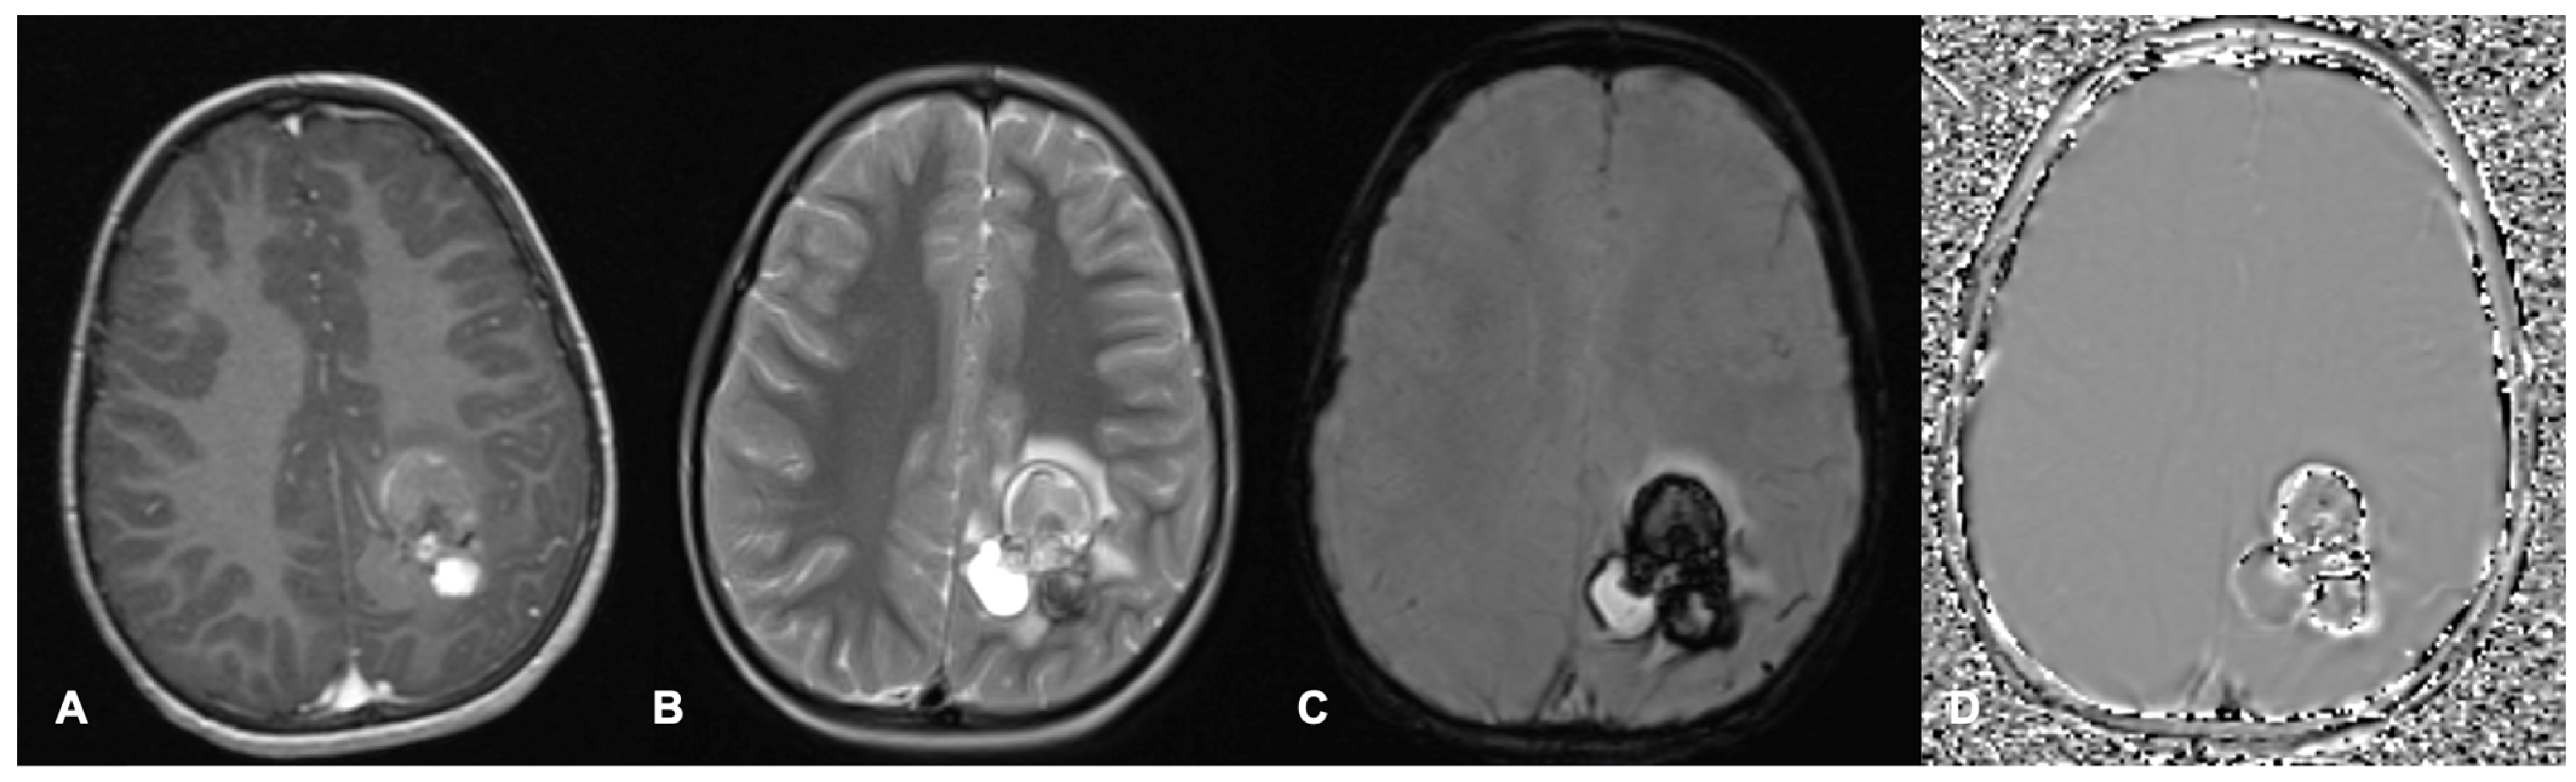

Figure 2.

Axial MRI brain scan of a left parietal cavernous malformation in a 7-year-old boy. (A) shows a heterogeneously contrast-enhanced lesion on post-contrast T1. (B) Heterogenous T2 signal within the lesion with surrounding oedema. The lesion demonstrates increased susceptibility on SWI (C) with signal dropout in the filtered phase (D) in keeping with haemorrhage.